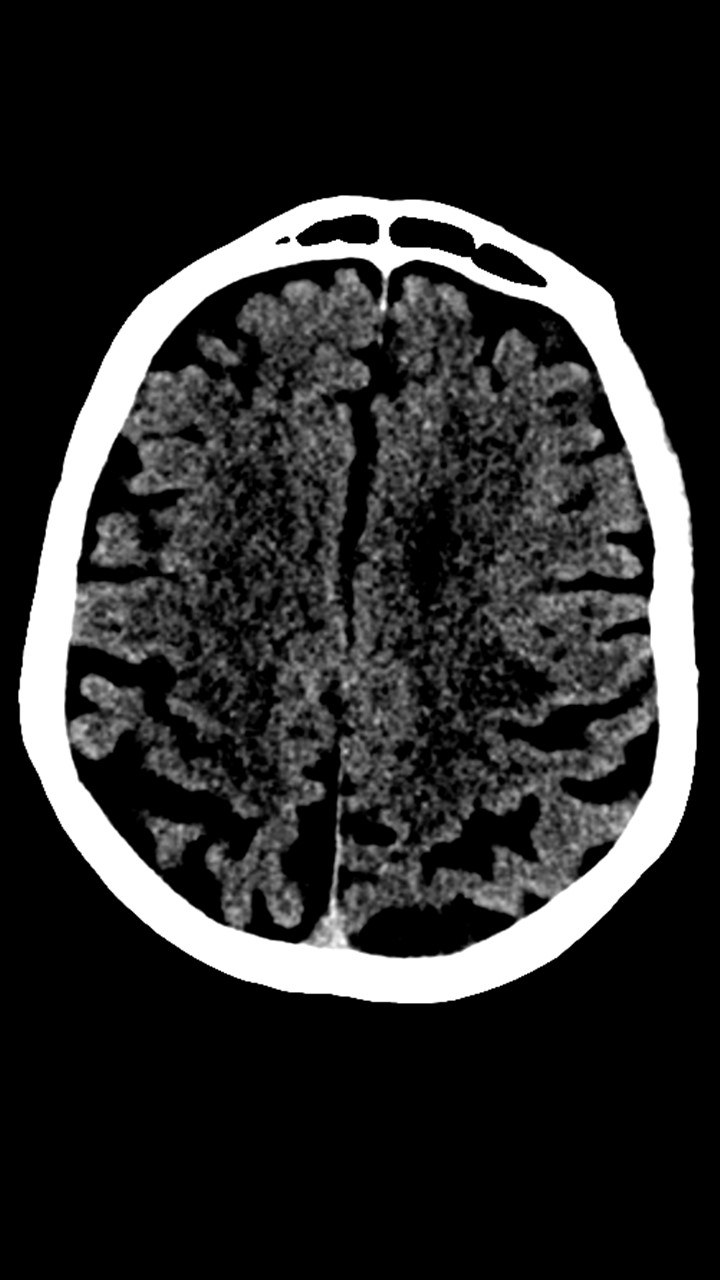

Hallazgos de TC de craneo:

• Cambios de leucoaraiosis periventricular.

• Hay zonas de hipodensidad subcortical fronto-parietal superior predominantemente izquierdas, de aspecto inespecíficos.

• Los halazgos son inespecificos, ante la ausencia de patología hemorragica aguda se decide continuar con el protocolo habitual.

Vasos del polígono sin claros signos de oclusion. No se aprecian alteraciones de la densidad del parénquima cerebral. No se aprecian signos de sangrado. tamaño ventricular y cisternas de la base sin alteraciones.